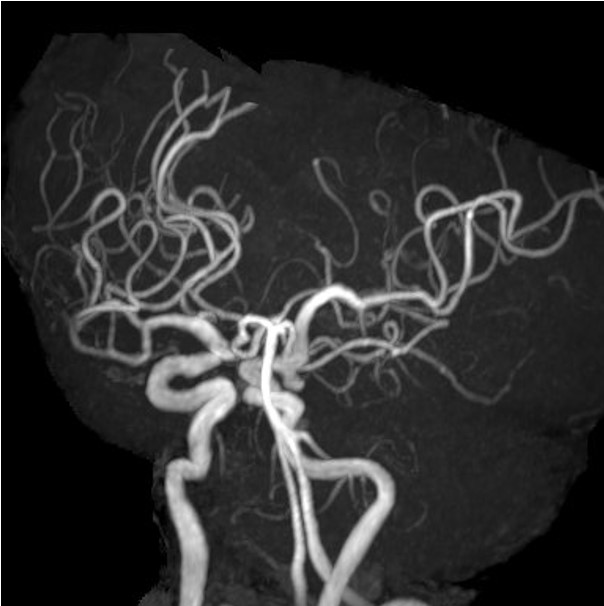

脳動脈瘤

脳動脈瘤が破裂すると、くも膜下出血を引き起こし命に関わることがあります。

MRA